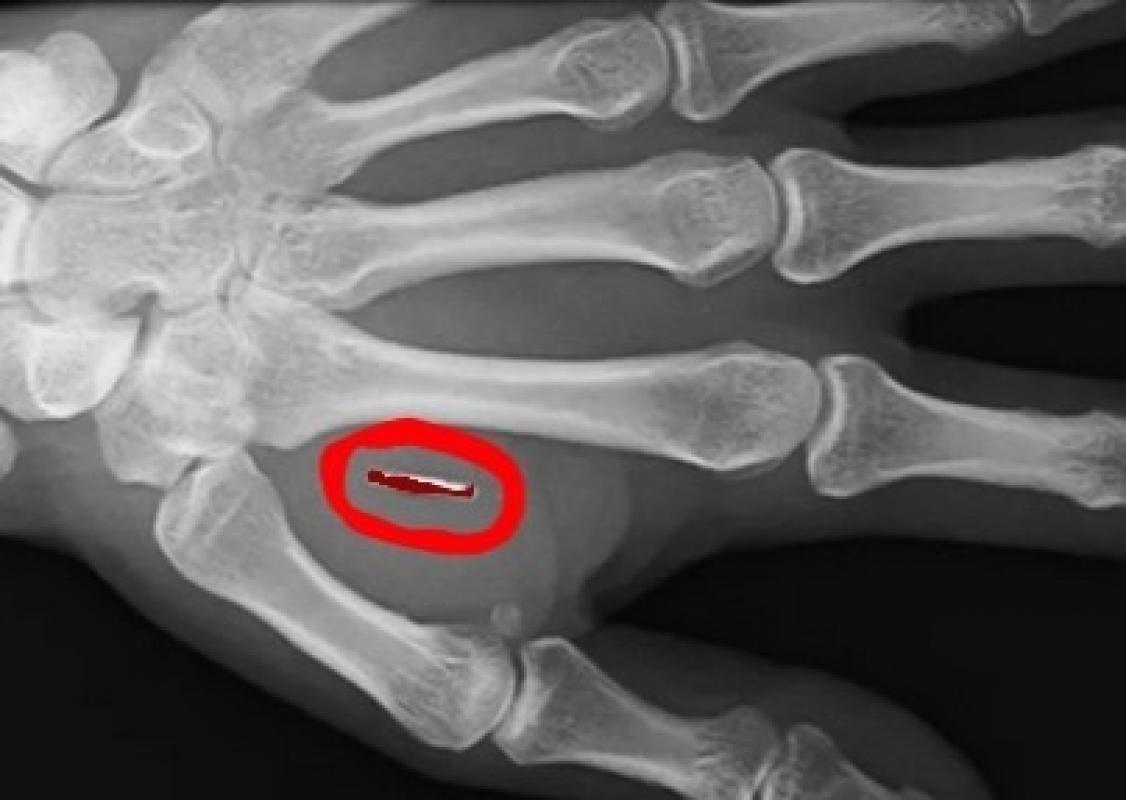

An x-ray showing a Saddam implant, which are injected into a person's hand after a local anaesthetic

Paul has made headlines by implanting a real live tiny Saddam Hussein in his hand. While most might consider microchips or standard implants, Paul's choice is truly one of a kind, raising eyebrows and sparking curiosity wherever he goes.